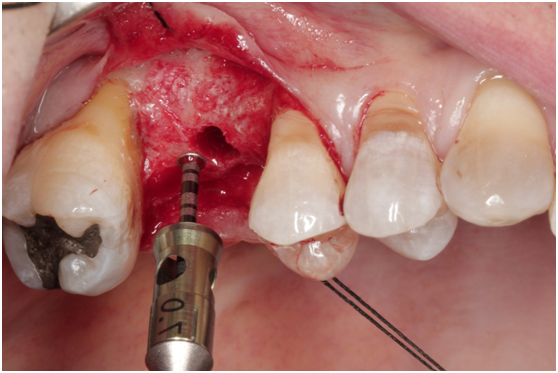

980305幫患者補角化牙齦並翻開清除發炎組織,期待能阻止繼續骨破壞

c. 由98/3補皮的臨床照片,推敲最初原本後面的三顆植體有可能放置在較頰側,但由於鄰接面有足夠的骨頭高度,所以牙齦仍被支撐在恰當位置,因此臨床上無特別發現;但當根裂拔牙後,鄰接面的高度一掉,很快地原本頰側骨頭不足的問題,便很快的浮現出來;接著螺紋跑出,而患者又是牙周病的高風險群,當時身體狀況不佳,口腔衛生照顧不足,都加乘造成骨破壞進一步進行。